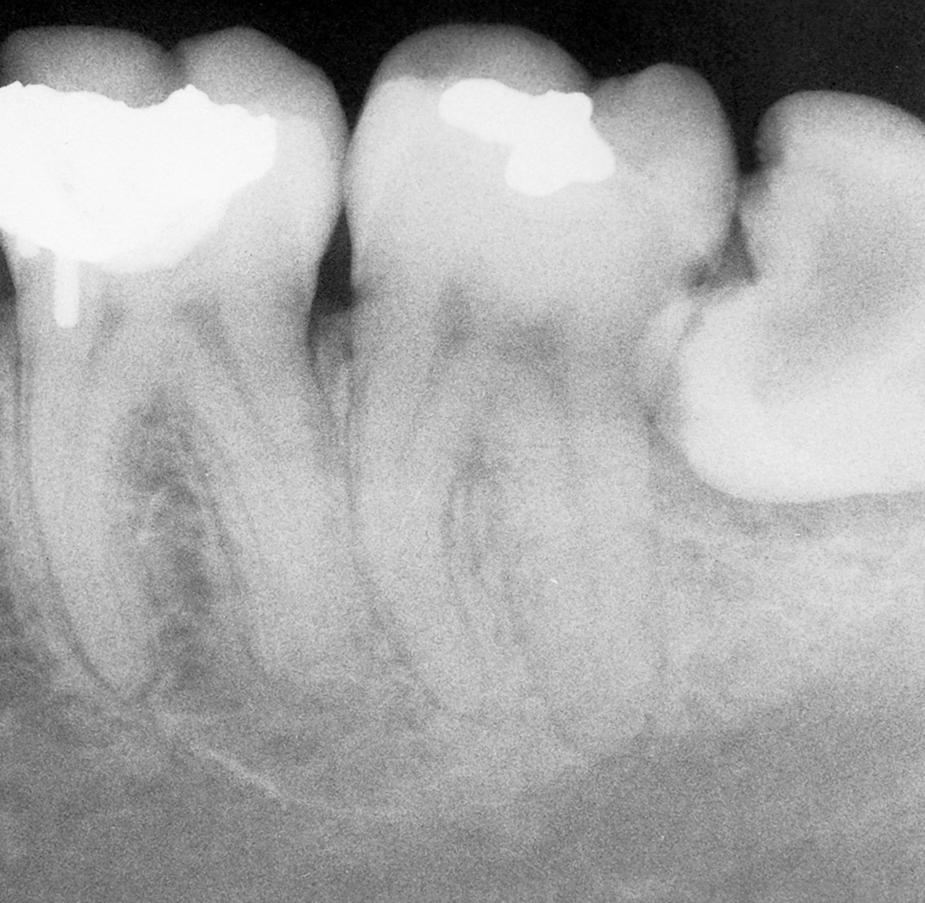

Erupted teeth adjacent to impacted teeth are predisposed to periodontal disease ( Figs. 10.1 and 10.2 ). The mere presence of an impacted mandibular third molar decreases the amount of bone on the distal aspect of an adjacent second molar. Because the most difficult tooth surface to keep clean is the distal aspect of the last tooth in the arch, patients commonly have gingival inflammation with apical migration of the gingival attachment on the distal aspect of the second molar. With even minor gingivitis, the causative bacteria gain access to a large portion of the root surface, which results in the early formation of periodontitis. Patients with impacted mandibular third molars often have deep periodontal pockets on the distal aspect of the second molars, even though they have normal sulcular depth in the remainder of the mouth.

Fig. 10.1, Radiograph of a mandibular third molar impacted against a second molar with bone loss resulting from the presence of a third molar.

Fig. 10.2, Radiographs showing variations of a mandibular third molar impacted against a second molar with severe bone loss resulting from periodontal disease and a third molar.